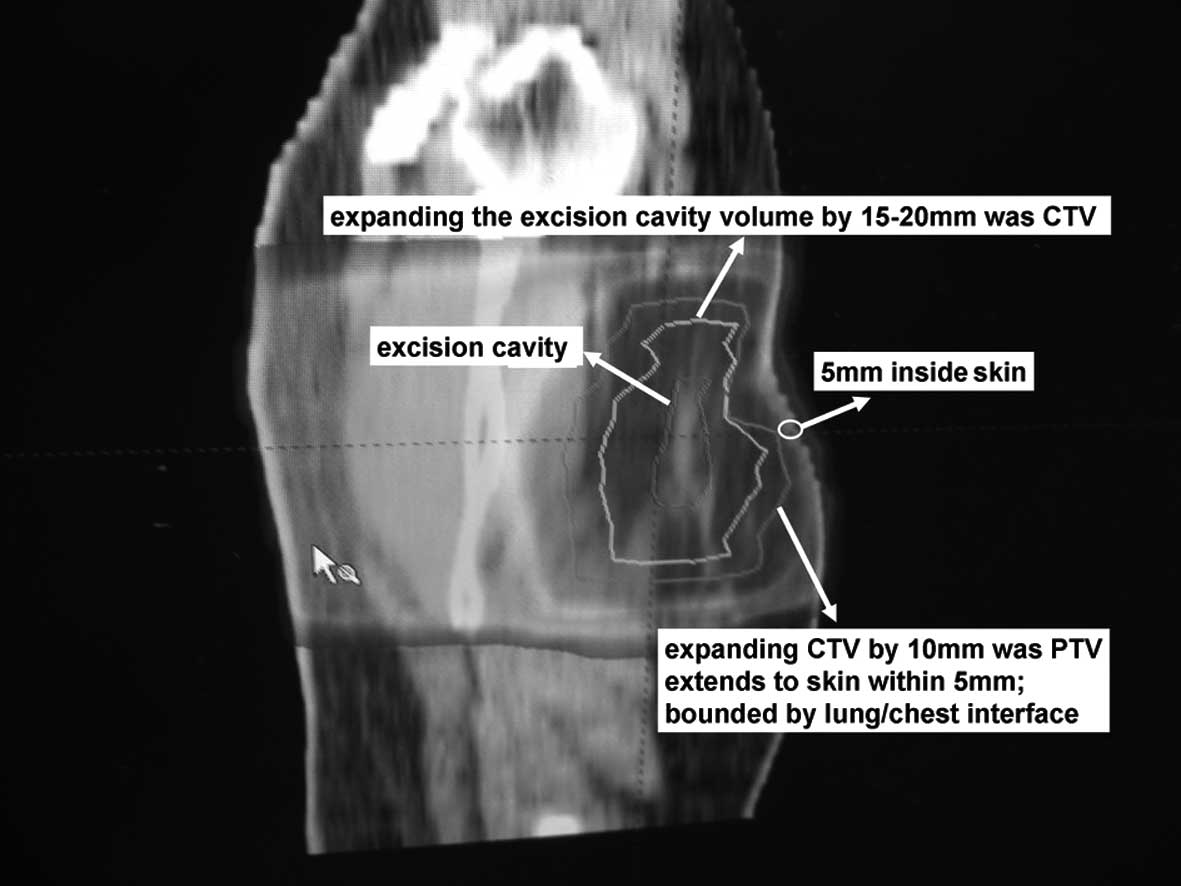

Local therapy (surgery and radiation therapy) Surgery is the main treatment for stage I breast cancer. These cancers can be treated with either breast-conserving surgery (BCS; sometimes called lumpectomy or partial mastectomy) or mastectomy.

What is the treatment for BCS?

Women who have BCS are treated with radiation therapy after surgery. Women who have a mastectomy are typically treated with radiation if the cancer is found in the lymph nodes.